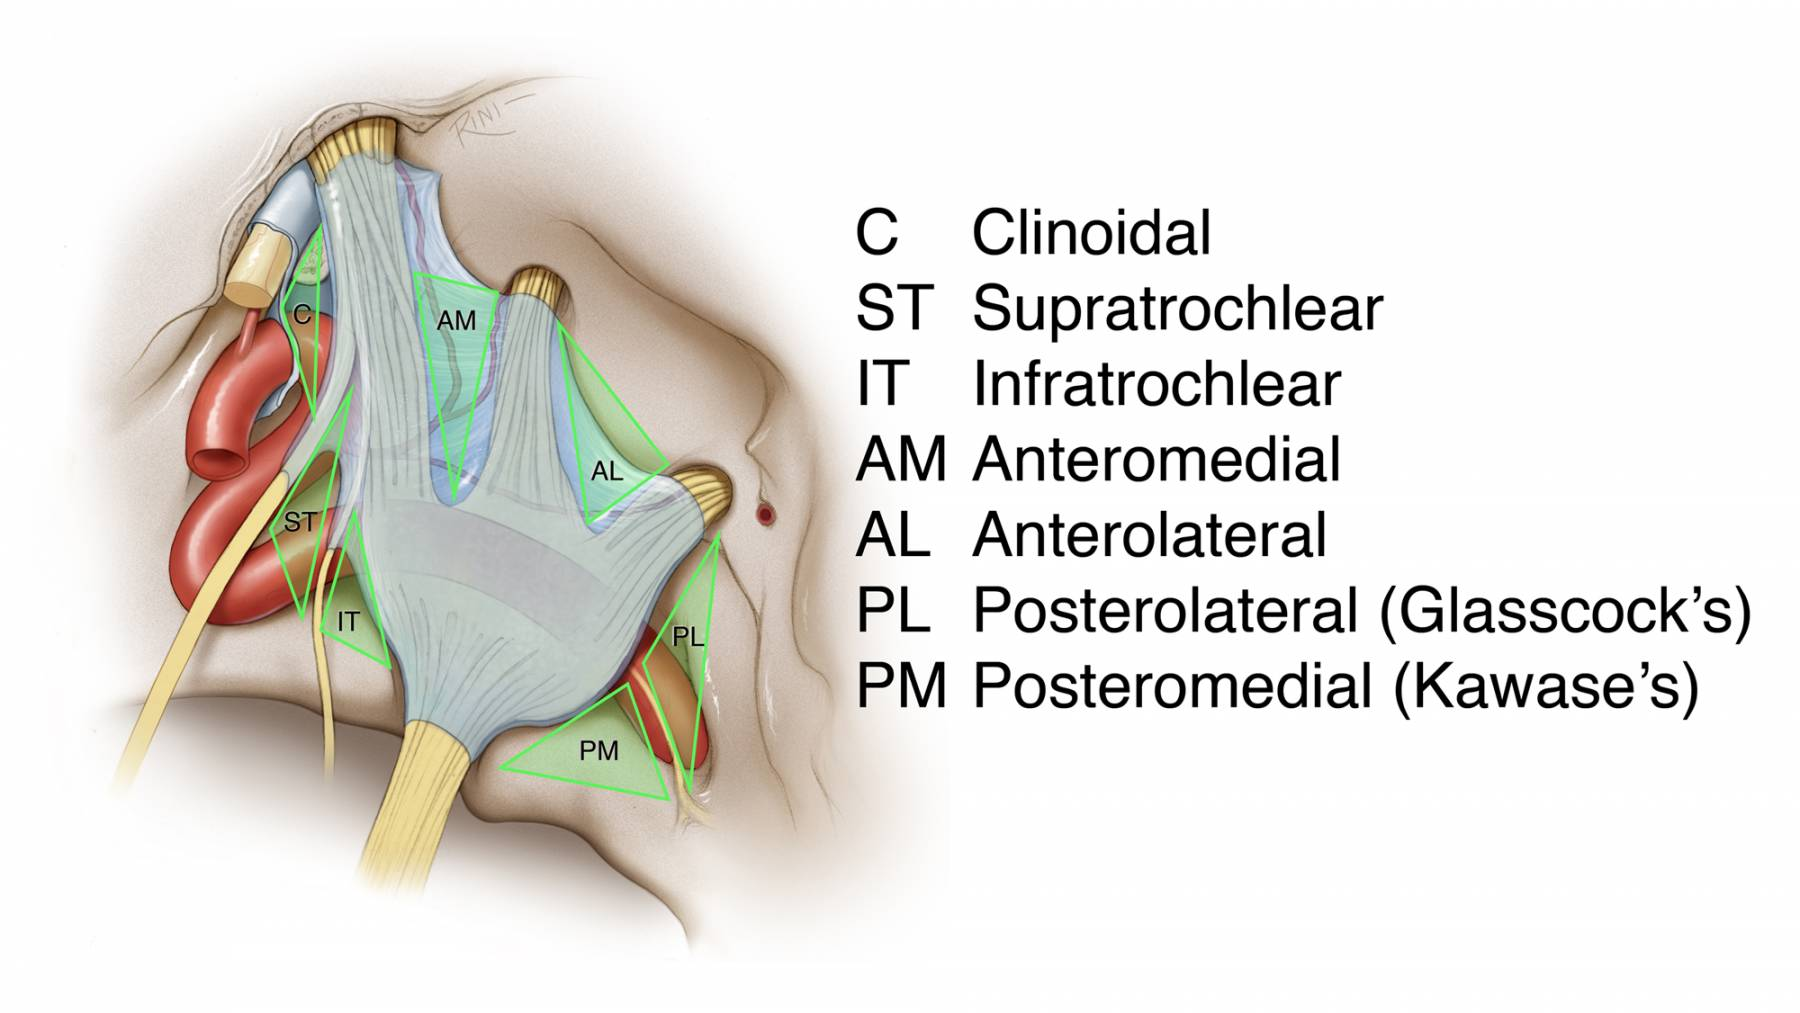

图3:硬膜外入路行右侧海绵窦的手术学解剖。颞前-眶颧开颅及硬膜外前床突切除术已完成,眶上裂的外侧缘已显露(左上图,此时硬膜外前床突切除术其实尚未完成,译者注)。在眶上裂的外侧缘处切断额颞或脑膜眶硬膜返折,将海绵窦外侧壁的外层从内层上剥离。因此,掀开海绵窦外侧壁的外层(脑膜层),即可显露融入外侧壁内层的颅神经(右上图)。

切断脑膜中动脉,继续向后内侧剥离硬膜,即可暴露岩浅大神经,其通常行于岩骨段颈内动脉上方,故可作为其定位标志。沿中颅窝剥离硬膜的内侧界为前岩床突硬膜返折,后界为岩骨嵴(左中图)。床突旁区域的放大观(右中图)。注意,经Parkinson三角进入硬膜内是可能的(译者认为是“海绵窦内、硬膜间”,译者注)。进一步剥除海绵窦外侧壁的内层(左下图)。病灶经外侧壁侵犯海绵窦的通道也即为手术进入海绵窦的径路。此时可见以下中颅窝三角:前内侧三角(三叉神经眼支和上颌支之间)、前外侧三角(三叉神经上颌支和下颌支之间)、后外侧三角(即Glasscock三角,三叉神经下颌支和岩浅大神经之间)、后内侧三角(即Kawase三角,三叉神经下颌支外侧与岩浅大神经后方区域)。最后一图展示了去除中颅窝底和内听道顶壁部分骨质后的解剖(右下图)。(感谢Rhoton教授对图片的授权)

图4:海绵窦区的硬膜内入路解剖。大型肿瘤应联合硬膜内及硬膜外入路。(感谢Rhoton教授对图片的授权)

经Parkinson三角(即滑车下三角)是处理硬膜内/海绵窦内肿瘤的合适径路。在天幕游离缘暴露动眼神经和滑车神经,在滑车神经走行的下方切开硬膜。向下延伸硬膜切口形成一硬膜辦,将其翻开至三叉神经半月节上方。切除肿瘤时,需注意保护外展神经,该神经常可分为2-5支神经束。(该段即为Dolenc入路在硬膜内直接打开海绵窦外侧壁的方法,译者注)

图7:显示了海绵窦的各个外科三角。肿瘤的生长方式常常决定了术中进入海绵窦的路径。在对神经移位方式进行预判后,滑车下三角和滑车上三角常可作为合适的入口。中颅窝前内侧、前外侧三角也常常需要被打开。注意Glasscock三角的位置,其用于颈内动脉岩骨段的暴露。